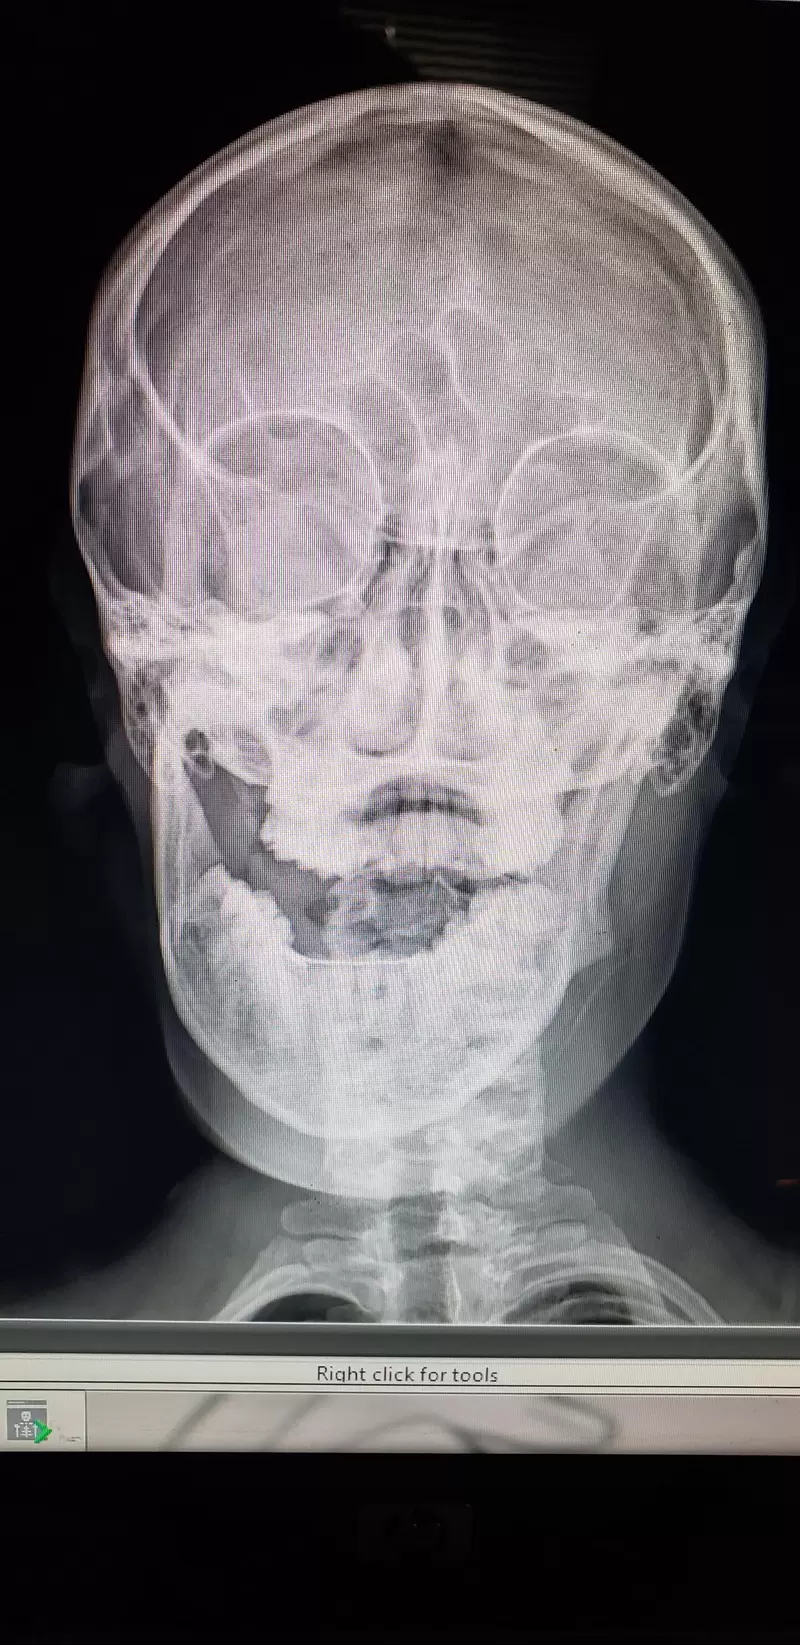

▼一位網友吃麥片的時候下巴脫臼惹

圖片來自:buzzfeed